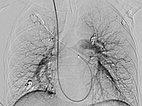

Completion DSA via the pulmonary trunk shows no more flow into the pulmonary AVMs.

Completion DSA via the pulmonary trunk in the parenchymal phase confirms complete occlusion of the pulmonary AVMs.